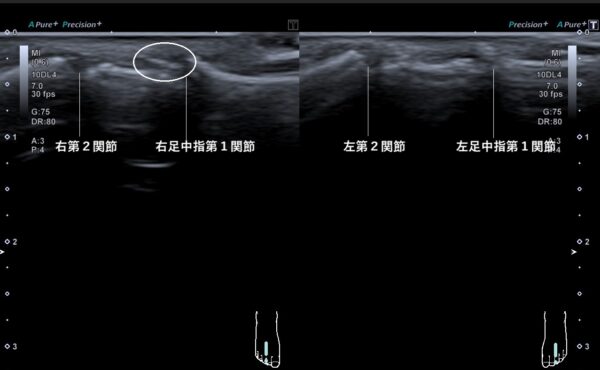

超音波画像観察を行うと中指の第1関節にある指伸筋腱に石灰がたまっていました(画像、丸の中の白い線)。